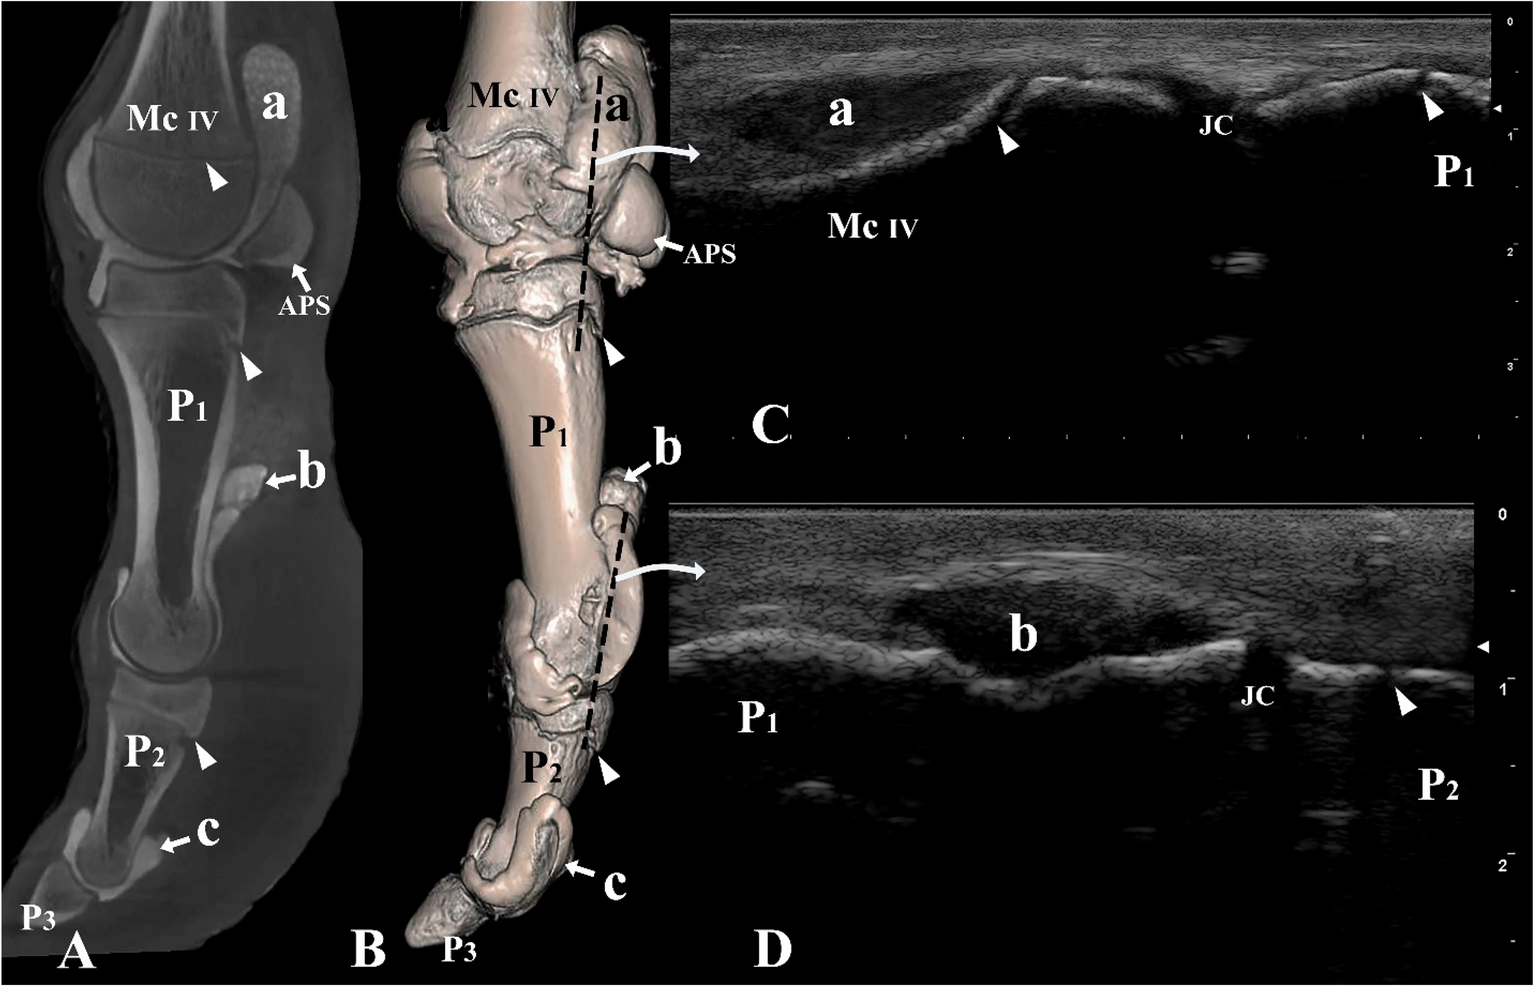

Figure 6

From: Arthrocentesis approaches to the phalangeal joints of the one humped camel (Camelus dromedarius)

Lateral view of the left digit IV. (A) Sagittal plane CT image; (B) three-dimensional reconstruction (the black dotted line indicating the placement of the ultrasound probe), (C) longitudinal lateral ultrasound image of the metacarpophalangeal joint, and (D) longitudinal lateral ultrasound image of the proximal interphalangeal joint. Mc IV distal end of metacarpal bone IV, P1 proximal phalanx, P2 middle phalanx, P3 distal phalanx, APS abaxial proximal sesamoid bone, a proximal palmar pouch of the metacarpophalangeal joint, b proximal palmar pouch of the proximal interphalangeal joint, c proximal palmar pouch of the distal interphalangeal joint, JC joint cavity. White arrowheads indicate the epiphyseal lines.